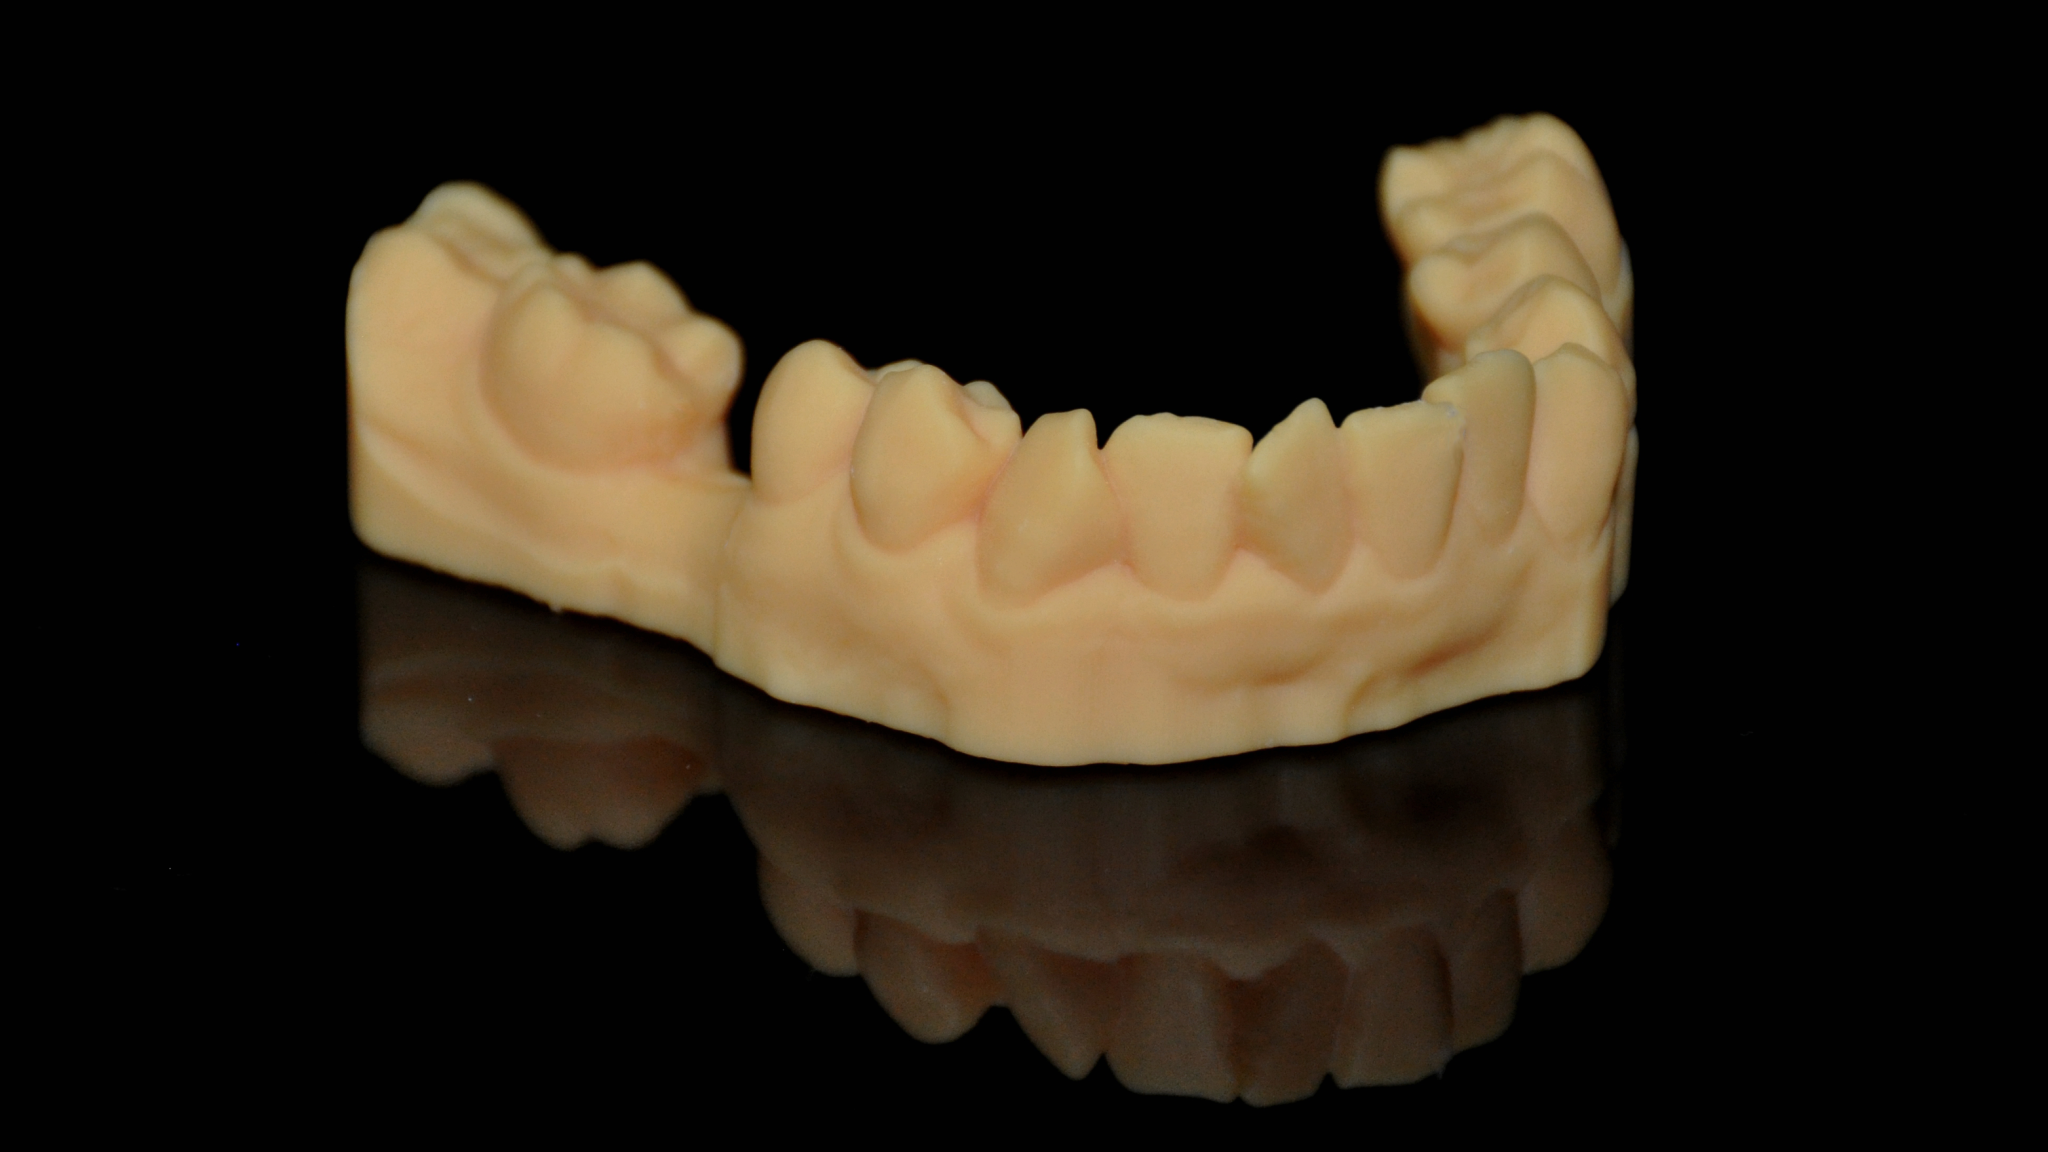

4. Print model & guide with AccuFab-D1

Printed model

Try-in on the printed model